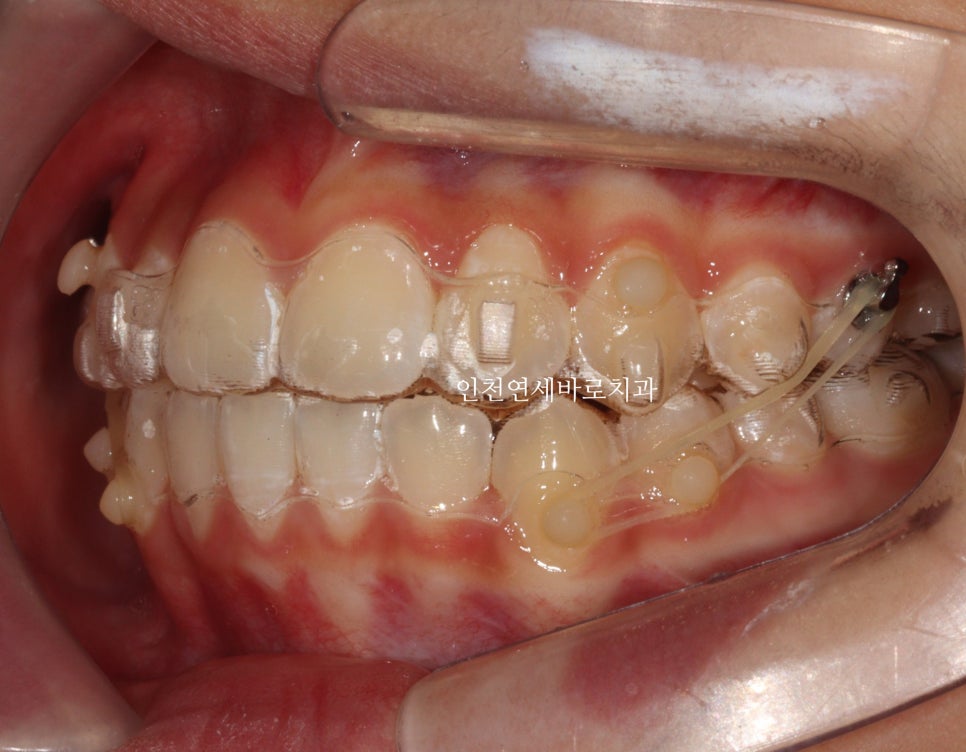

전 후 비교

인비절라인으로 치료하면 교합이 맞지 않는다. 라는 이상한 소문이 있습니다.

노하우와 경험, 실력이 있으면 문제없죠.

그래서 치료경험이 많은 곳을 잘 찾아 상담 받고 치료를 진행하시면 좋습니다

치아배열도 좋습니다.